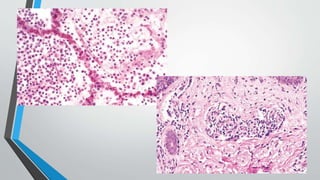

Mononuclear and Granulomatous Inflammation

• Granulomatous inflammation is a distinctive form of mononuclear inflammation

• Granulomatous inflammation is characterized by accumulation of activated

cases there is a central area of caseous necrosis.

Mononuclear and GranulomatousInflammation • Diffuse, predominantly mononuclear, interstitial infiltrates are a common feature of all chronic inflammatory processes. • They often are a response to viruses, intracellular bacteria, or intracellular parasites. In addition, spirochetes and helminths provoke chronic inflammatory responses. • Which mononuclear cell predominates within the inflammatory lesion depends on the host immune response to the organism. • Granulomatous inflammation is a distinctive form of mononuclear inflammation usually evoked by infectious agents that resist eradication and are capable of stimulating strong T cell–mediated immunity • Granulomatous inflammation is characterized by accumulation of activated macrophages called “epithelioid” cells, which may fuse to form giant cells. In some cases there is a central area of caseous necrosis.